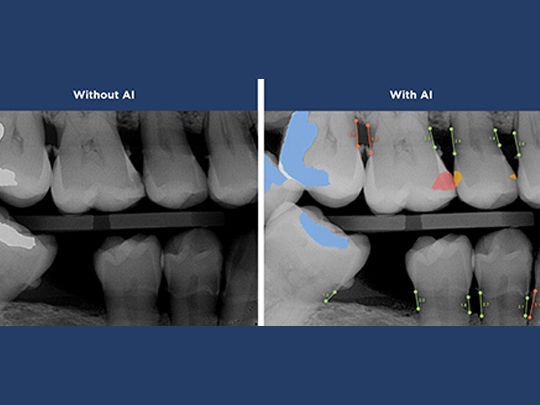

We use advanced artificial intelligence to assist in reading digital X-rays, helping us detect cavities, bone loss, and infection with greater accuracy—often before symptoms even appear.